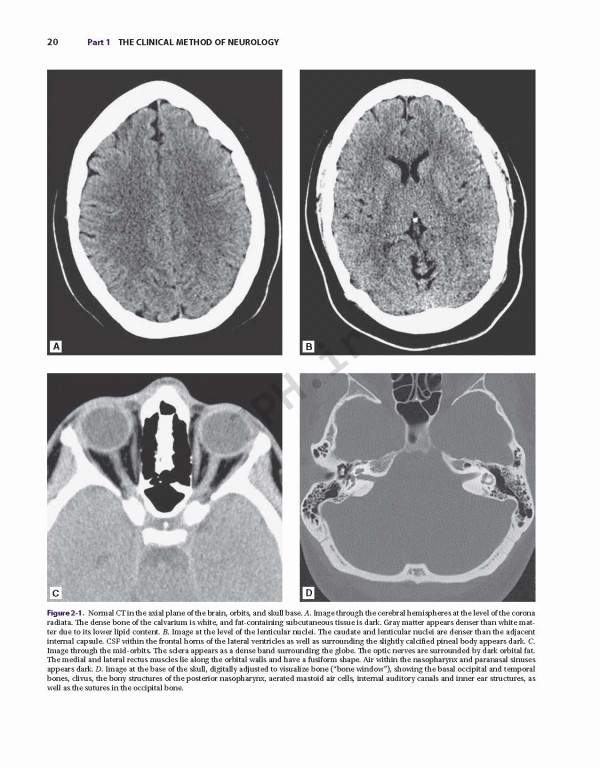

کتاب Adams and Victor's Principles of Neurology 11th Edition 2019، اصول نورولوژی آدامز و ویکتور یک کتاب مشهور که پزشکان را به درک عمیق از جنبه‌های اصلی بیماری عصبی، از جمله داده‌های بالینی و جدید علمی راهنمایی می کند. این متن دقیق و تجدید نظر شده و به روز شده‌، همچنان یک شاهکار در زمینه خود است و خواندنی ترین مرجع موجود. در صفحات آن، شما می توانید توصیفات انضباطی از داده‌های بالینی و توضیحات روشنی از روند بیماری‌های زمینه‌ای را پیدا کنید.

Adams and Victor’s Principles of Neurology is truly the classic text in its discipline --- a celebrated volume that guides clinicians to an in-depth understanding of the key aspects of neurologic disease, including both clinical and new scientific data. This meticulously revised and updated text remains the masterwork in its field, and the most readable reference available. Within its pages, you will find a disciplined presentation of clinical data and lucid descriptions of underlying disease processes.

•A rich, full-color presentation that includes many high-quality illustrations